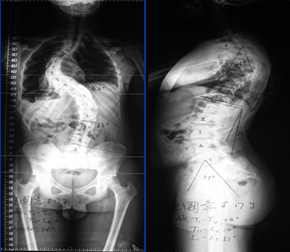

术后照片

第二次手术:侧凸矫正。患者外观畸形改善明显,身高继续增加5cm。